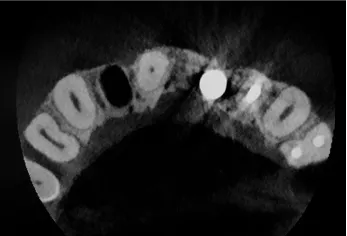

Precyzja projektu druku siatki bazuje na dokładności odwzorowania kształtu kości w stożkowej tomografii komputerowej CBCT, co zapewnia ich dobre przyleganie do podłoża kostnego oraz ogranicza powstawanie powikłań w postaci obnażania się siatek. Precyzja projektu oraz materiał, z którego wykonana jest siatka (biozgodny stop tytanu), powodują, że obnażenie się siatki nie zaburza procesu gojenia i regeneracji kostnej.

Wymaga jedynie większej ilości kontroli pozabiegowych oraz wzmaga czujność higieniczną zarówno ze strony lekarza, jak i pacjenta. Ten rodzaj odbudowy kostnej stosowany jest w sytuacjach złożonych, trójwymiarowych 3D ubytków kości, przy których standardowe metody odbudowy są niewystarczające. Ilość kości, którą możemy uzyskać, stosując tę metodę, to nawet kilka centymetrów sześciennych.

Metoda rekonstrukcji kostnej w oparciu o indywidualnie drukowane siatki z tytanu dla implantacji wszczepów śródkostnych stosowana jest najczęściej jako dwuetapowa. W pierwszym etapie odbudowywana jest kość, natomiast implanty wszczepiane są po okresie 4–6 miesięcy. Na wgojenie implantów oczekujemy od 4 do 6 miesięcy w zależności od miejsca ich lokalizacji. Siatka tytanowa po spełnieniu swojej funkcji rusztowania dla odbudowującej się kości jest następnie usuwana w dniu wszczepienia implantu. Jeżeli kość spełnia odpowiednie warunki, istnieje możliwość zastosowania modyfikacji siatki tytanowej, która umożliwia jednoczesne wprowadzenie implantów wraz z odbudową kostną.